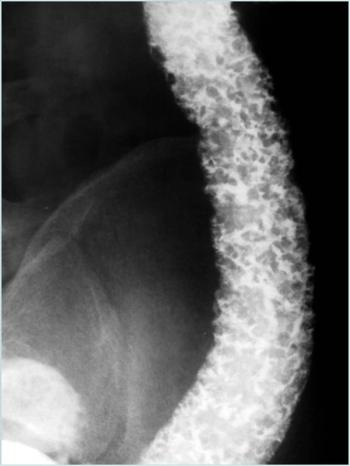

Can you diagnose this patient with bloody stool?